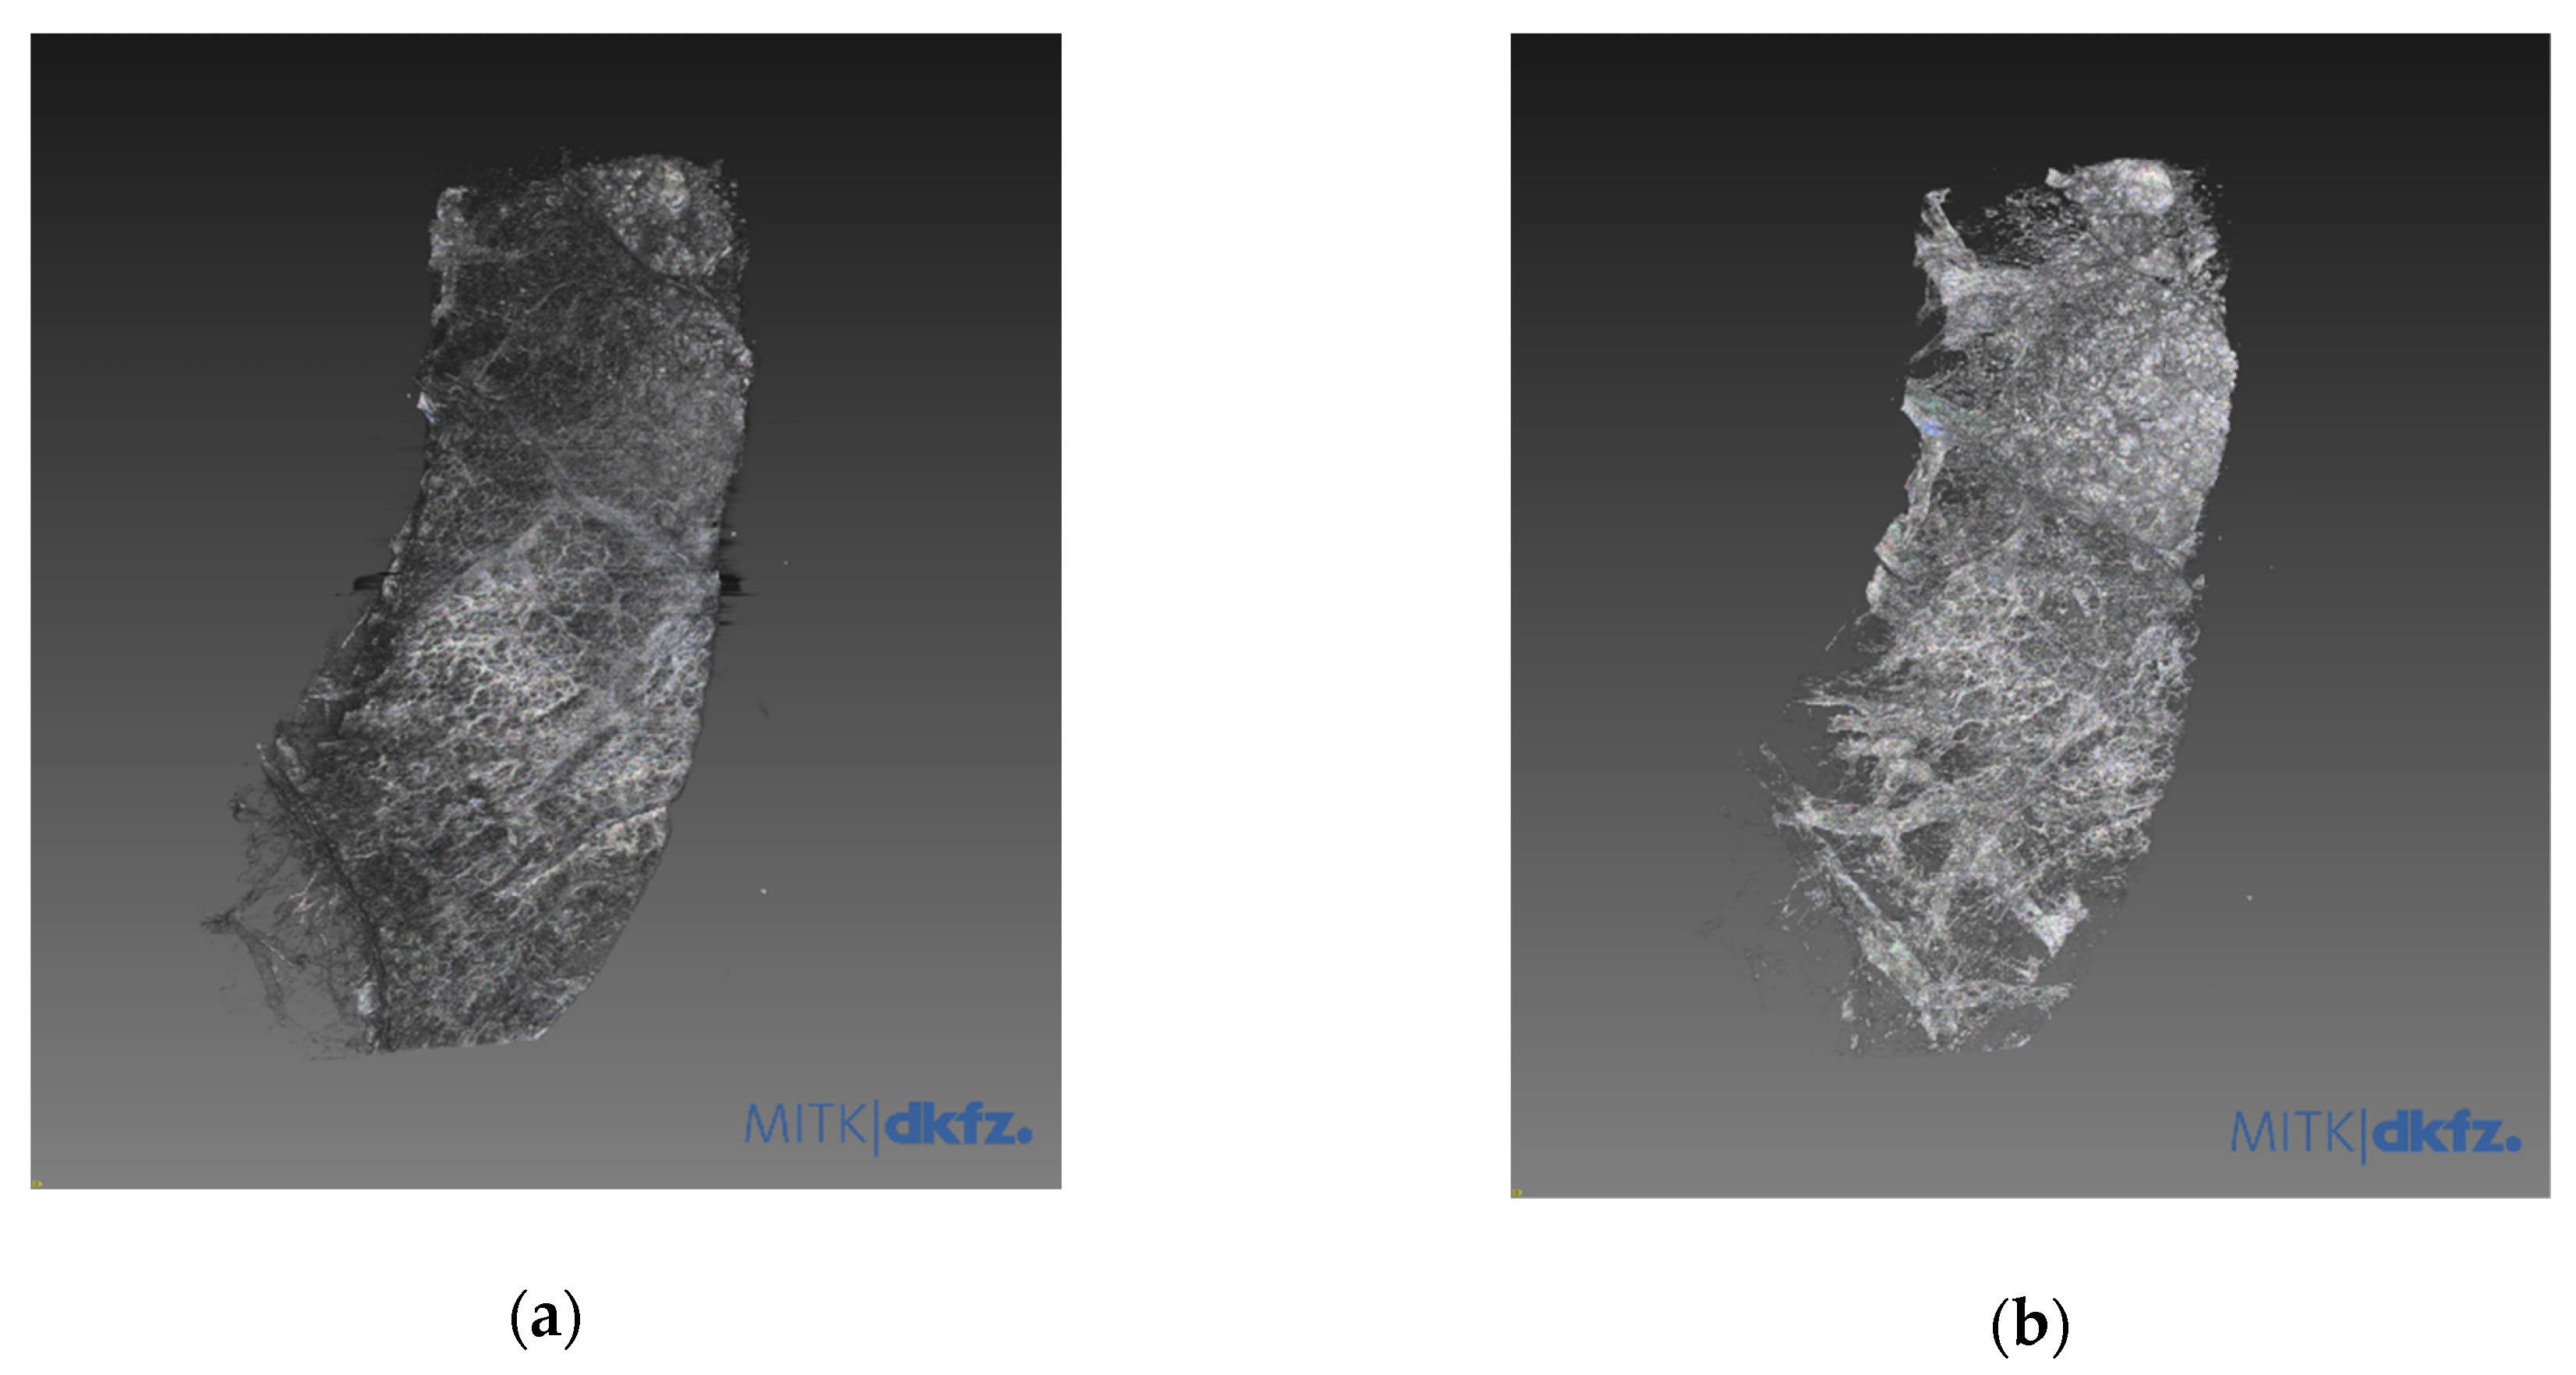

3.1. Refraction-Contrast Synchrotron Tomographic Images of Lung Tissue Including Cancer and 3D Reconstruction